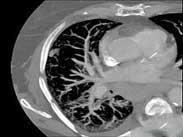

老年人肺栓塞癥狀

• 老年人肺栓塞

628健康網(wǎng)為您分享有關(guān)老年人肺栓塞的癥狀,老年人肺栓塞的治療方法,老年人肺栓塞的預(yù)防知識(shí),老年人肺栓塞的癥狀圖片,老...